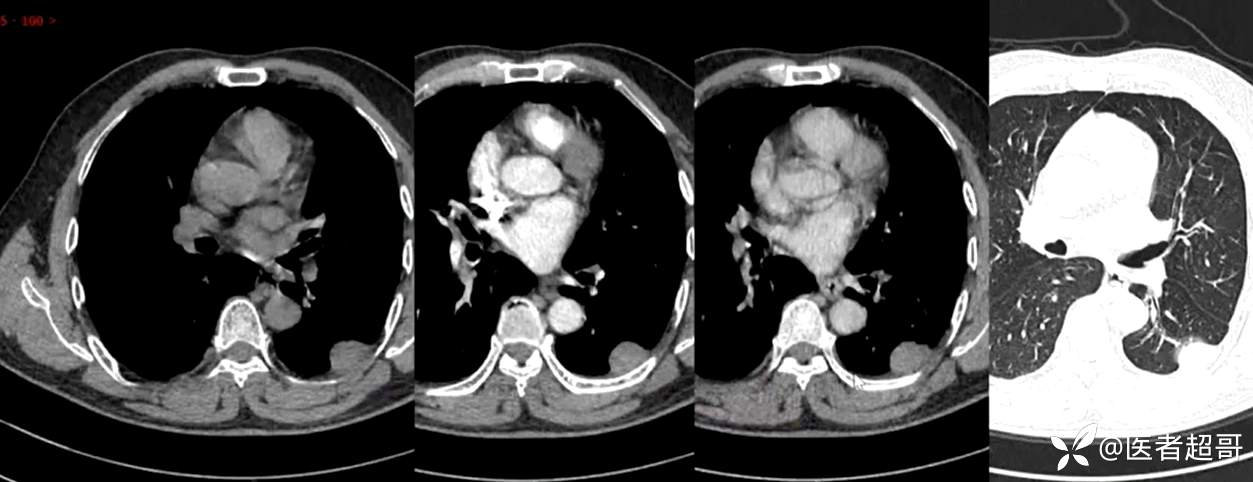

现病史:患者5月前因咳嗽、咳痰于当地医院就诊,完善胸部CT提示:胸膜多发占位,期间患者无胸闷、气紧、咳嗽、咳痰、心慌等不适,患者于我院门诊行胸部CT提示:左下胸膜增厚并见多个软组织密度结节影局限性凸起,较大者大小约3.5x2.2cm,增强扫描呈持续性轻度强化,考虑肿瘤性病变可能性大;门诊遂以:胸膜肿瘤收入我科。